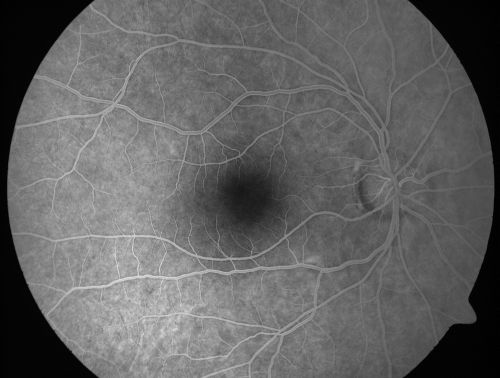

Occult Maculopathy - Thin Fovea on OCT and Normal Color VA, Photos, FA VA 20/80 OU

45-year-old man Normal FA